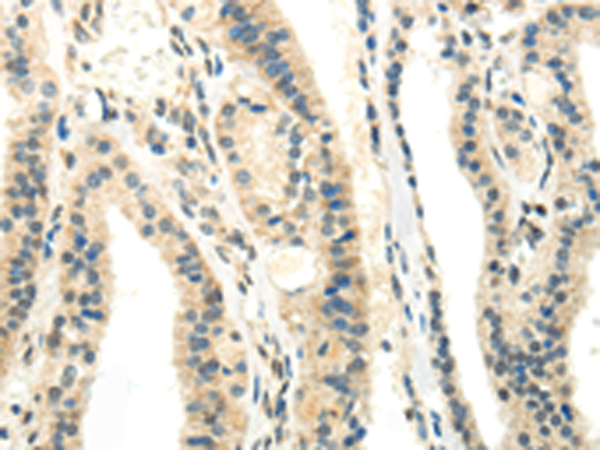

分类: 科研抗体货号: P10689别名: FLDB; LDLCQ4应用: IHC反应种属: Human, Mouse, Rat